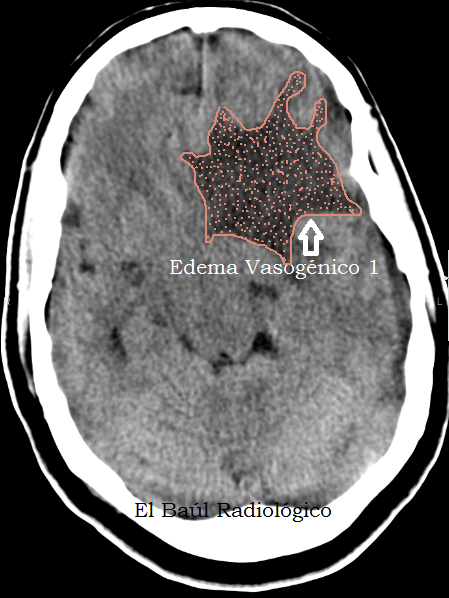

El más importante de todos es el edema vasogénico, porque es un signo indirecto de la existencia de un proceso patológico intracraneal, que podría pasar desapercibido en una exploración de TC o TRM. En este tipo de edema se produce un aumento de la permeabilidad de los capilares normales del cerebro porque están comprimidos por una lesión ocupante de espacio intracraneal o porque hay un fenómeno de angiogénesis tumoral que produce arteriolas patológicas. El edema vasogénico cerebral puede estar producido por un tumor maligno, uno benigno, una infección o un traumatismo. El líquido extravasado difunde por la sustancia blanca cerebral contorneando la corteza, motivo por el que se presenta como un área hipodensa de contorno digitiforme. Suele producir efecto de masa importante. ¿Pero, cual es la causa que produce el edema vasogénico? La utilización de contraste suele solucionar esta duda.

(Vasogenic edema, is an indirect sign of the existence of an intracranial pathologic process that could go undetected in a CT or MRI scans. In this type of edema there is an increase of permeability of normal brain capillaries that are compressed by a intracranial space occupying lesion or because there is a phenomenon of tumoral angiogenesis. The cerebral vasogenic edema can be caused by a malignant tumor, a benign, infection or trauma. The extravasation of liquid diffuses throught cerebral white matter, outlining the cortex, why is presented as a hypodense digitiform area. It usually causes significant mass effect. But, what is the cause that produces vasogenic edema? The use of iodinated endovenous contrast usually solve this doubt)

FIGURA 1) En esta imagen se aprecia edema vasogénico en la sustancia blanca del lóbulo frontal izquierdo. No podemos identificar la causa.

(This image shows a large area of vasogenic edema in the white matter of the left frontal lobe).